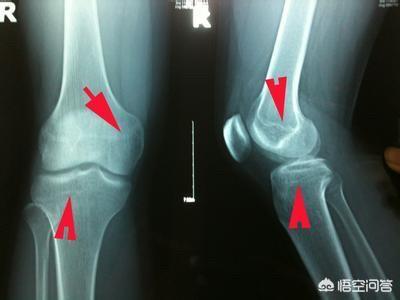

D'un point de vue médical, après les règles, tant que l'épiphyse ne s'est pas refermée, il est encore possible de grandir. Si vous voulez vraiment savoir si vous pouvez encore grandir, le mieux est d'aller à l'hôpital et de passer une échographie pour vérifier votre âge osseux. Tant que votre âge osseux ne dépasse pas votre âge, vous avez la possibilité de grandir.

Par conséquent, si la fille a eu ses règles pendant un an, selon la norme, le développement est déjà tardif, vous pouvez prendre l'enfant pour vérifier l'âge osseux, savoir si l'épiphyse de l'enfant est fermée, si elle a été fermée, alors la moitié de l'année n'a pas grandi, ce qui signifie que l'enfant a cessé de grandir.